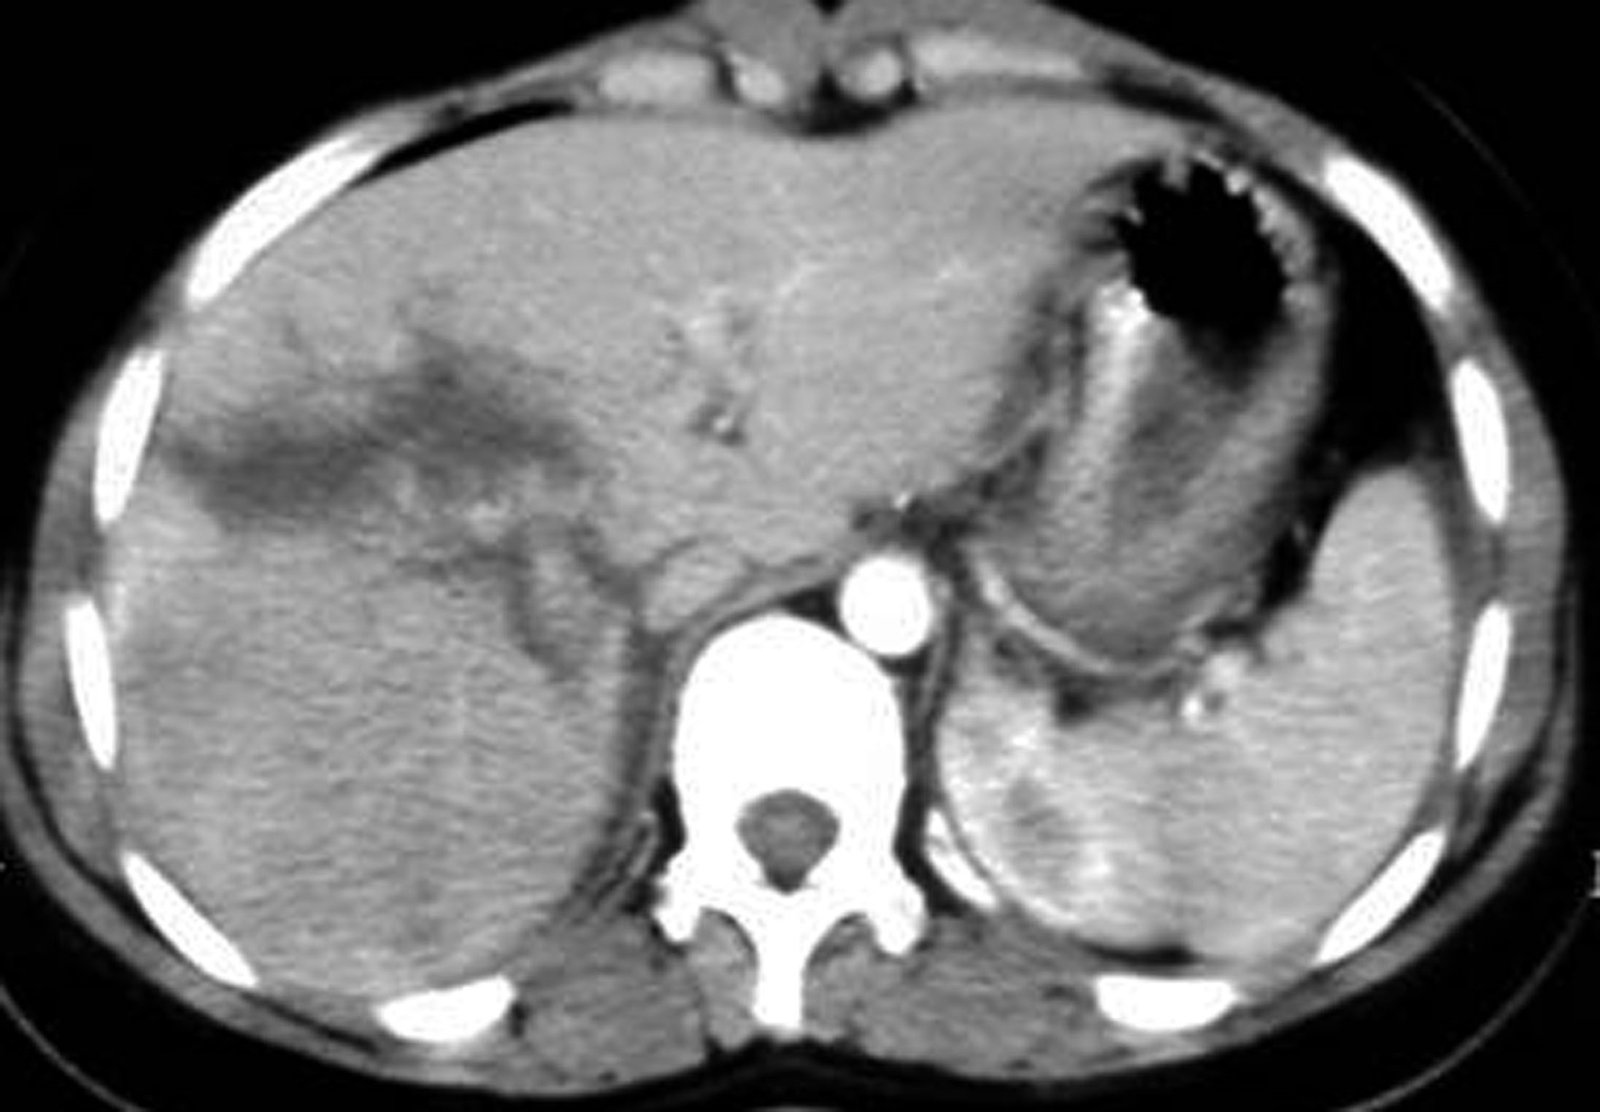

Qaraciyərin açıq zədələnmələri adətən əməliyyat vaxtı dəqiqləşdirilir, lakin USM və KT ilə də bəzi zədələnmələr görünə bilər. Küt zədələnmələrin diaqnozu isə adətən KT ilə qoyulur (Şəkil 7).

travma img 23  travma img 24

Şəkil 7. Qaraciyərin travmasının KT və intraoperativ görüntüsü